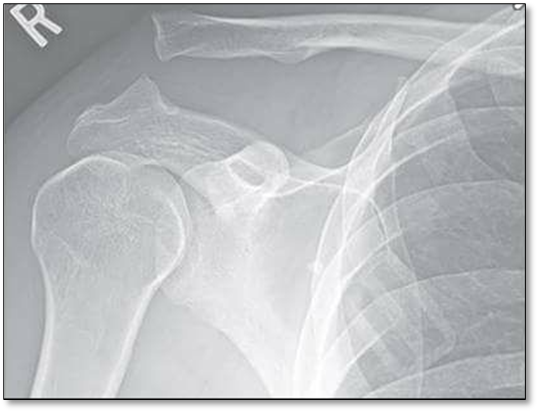

Hình ảnh trật khớp trên Xquang

2. Khái niệm trật khớp cùng đòn

Là một chấn thương vai thường gặp (thường do chấn thương thể thao hoặc do ngã đập vai xuống nền cứng). Thường gặp trong các vận động viên xe đạp, trượt tuyết hoặc đá bóng. Trật khớp cùng đòn khi lực tác động vào phía ngoài xương đòn dẫn đến trật khớp ở mức độ nhẹ, trung bình hoặc nặng. Ở mức độ nhẹ, trung bình thì các dây chằng liên quan căng giãn hoặc đứt một phần. Ngược lại ở các trường hợp nặng thì các dây chằng néo giữ xương đòn xuống dưới bị đứt, khi đó đầu ngoài xương đòn bị bật lên, có thể thấy da phía ngoài nhô lên.